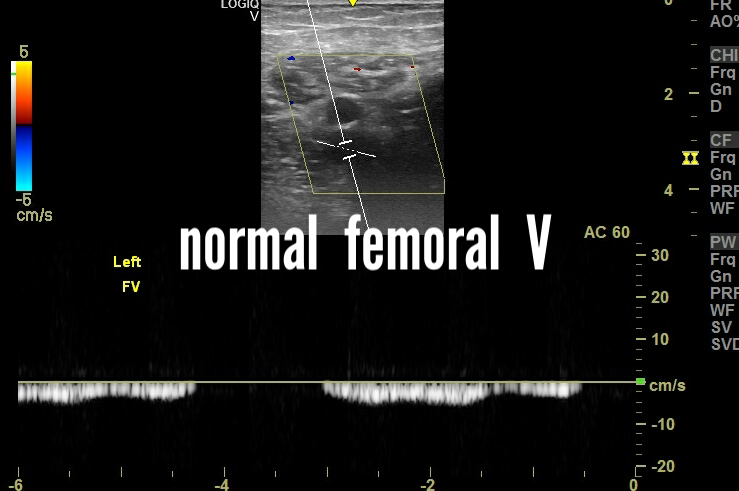

First let's have a look at some examples of normal veins in 2 different patients.

The above spectral Doppler ultrasound images are of 2 healthy patients with mild respiratory phasicity of normal popliteal and femoral veins.